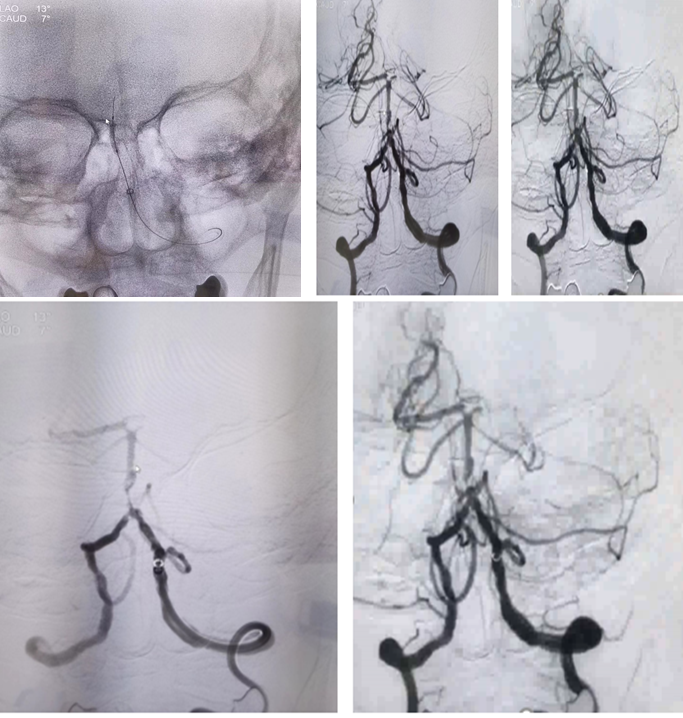

DSA

病历夹什么径技·第151期|串联营病历夹:京广连营_https://www.jmylbn.com_新闻资讯_第8张

病历夹什么径技·第151期|串联营病历夹:京广连营_https://www.jmylbn.com_新闻资讯_第9张

<<滑动查看下一张图片>>

结论:左侧颈动脉起始部位出现断流,右侧颈动脉没有明显代偿,血管形态较光滑。